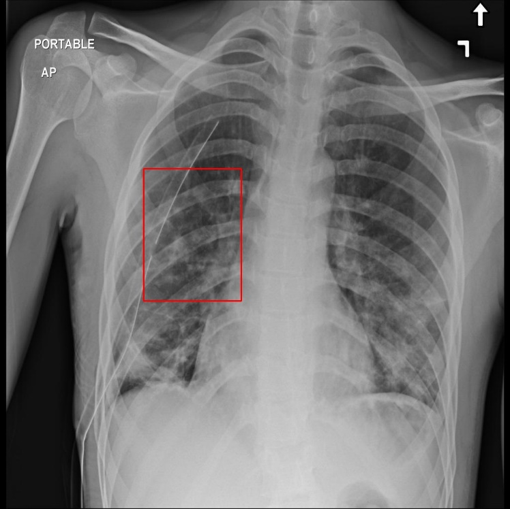

Figure 1: Examples of the five categories of X-ray images in the dataset, the first is a normal chest X-ray image without pneumonia, and the other four are images of four different types of pneumonia. The bounding boxes in the X-ray images are the area of the pneumonia lesions identified and marked by the doctor.

The dataset we employed consists of 20,012 X-ray images of pneumonia. As shown in Fig.1, there are five categories in the dataset, one category is normal X-ray images without pneumonia lesion, and the other four categories are X-ray images with different kinds of pneumonia. The pneumonia lesion areas of these four types of images are marked by highly-trained radiologists through bounding boxes, whose coordinates are available. We divided the pneumonia dataset into the training set and test set, and the rule of division is to randomly select 10% of images of each category to form the test set, and the remaining 90% is used as the training set. Each image is a single-channel chest X-ray with the resolution of 1024x1024. The dataset is available at https://god.yanxishe.com/23?from=god_home_list.